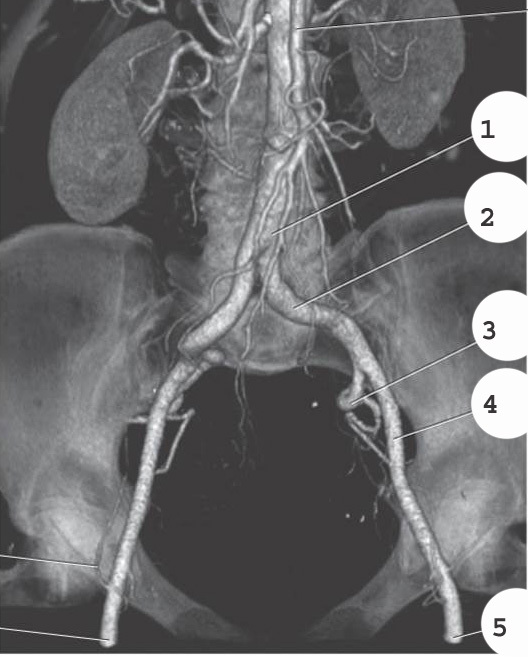

Aorta

2

Left common iliac artery

3

Left internal iliac artery

4

left external iliac artery

5

left femoral artery